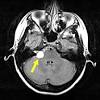

Paroxysmal Vertigo Attacks Chapter 6 The Paroxysmal Disorders

Paroxysmal Vertigo Attacks Chapter 6 The Paroxysmal Disorders from static.cambridge.org